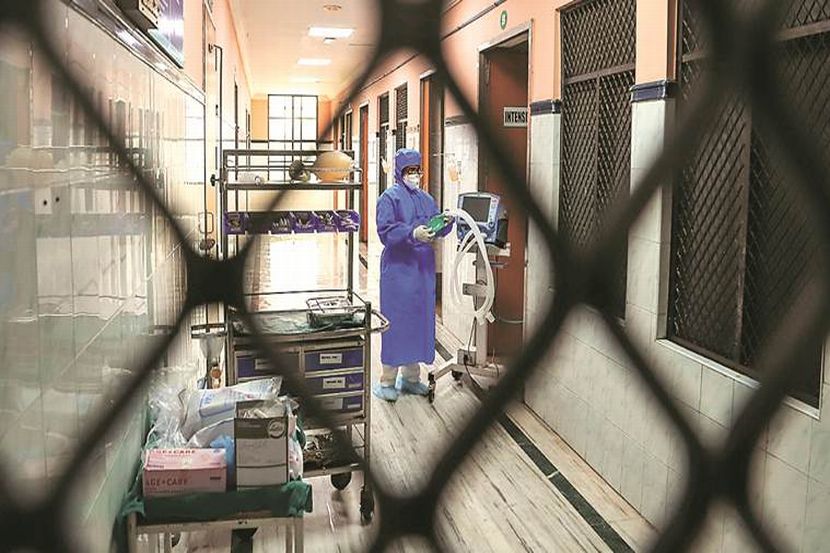

कोरोना रुग्णांची संख्या वाढतच असून शहराबरोबरच ग्रामीण भागातील नागरिकांनाही कोरोनाची मोठ्या प्रमाणात लागण होत असल्याने कोरोना बाधितांचा आकडा वाढतच चालला आहे. काही दिवसांआधी मोठ्या संख्येने आढळणारे रुग्ण आता कमी प्रमाणात आढळू लागले आहेत. आज ५ व्यक्तींचे अहवाल पॉझिटिव्ह आल्याने तालुक्यातील एकूण कोरोना बाधित रुग्णांची संख्या ६४७ झाली आहे. तर ऍक्टिव्ह पॉझिटिव्ह रुग्णांची संख्या ८७ झाली आहे. आज आणखी २० रुग्ण कोरोनातून बरे झाल्याने त्यांना सुटी देण्यात आली आहे. आता पर्यंत ५४३ रुग्ण कोरोनामुक्त होऊन घरी परतले आहेत.

तालुक्यात कोरोना रुग्णांची संख्या वाढतीवरच असली तरी संक्रमणाची गती मंदावली असल्याचे मागील काही दिवसांपासून पाहायला मिळत आहे. मोठ्या प्रमाणात आढळणारे कोरोनाचे रुग्ण काही अंशी मंदावले असल्याचे निदर्शनास येत आहे. तालुक्यात आज पाच व्यक्तींचे कोरोना अहवाल पॉझिटिव्ह आल्याने नागरिकांना दिलासा मिळाला आहे. आज १६ तपासणी अहवाल प्राप्त झाले असून ५ पॉझिटिव्ह तर ११ अहवाल निगेटिव्ह आले आहेत. आज एकही रॅपिड अँटीजेन चाचणी करण्यात आली नाही किंवा कोण्याही व्यक्तीचे स्वाब तपासणी करिता पाठविण्यात आले नाहीत. अद्यापही ३३ स्वाबचे अहवाल प्राप्त होणे बाकी आहे. पॉझिटिव्ह रुग्णांपैकी १७ रुग्ण कोविड केयर सेंटरला भरती असून २० रुग्ण यवतमाळ शासकीय रुग्णालयात उपचार घेत आहेत. तर ५० रुग्णांवर होम आयसोलेशनमध्ये उपचार सुरु आहेत. सध्यास्थितीत ४० व्यक्तींना संस्थात्मक विलीगीकरणात ठेवण्यात आले आहेत.